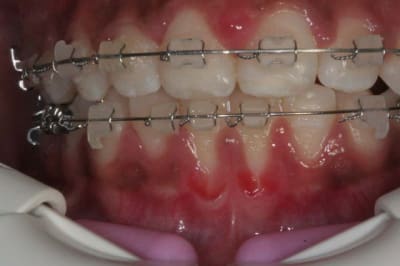

voici l'état de la gencive en fin de TTT. ORTHO

dois-je épaissir cette gencive très fine, (donc fragile), en face de 31/41 ?

@+ Bjc.

bonsoir ,s'il fallait greffer tous les jeunes patients qui finissent l'ortho avec une gencive comme ceci c a d: fine mais pas de tension des freins, on n'arrêterait pas.

maintenant,si on veut appliquer le sacro- saint principe de précaution ......tout est permis